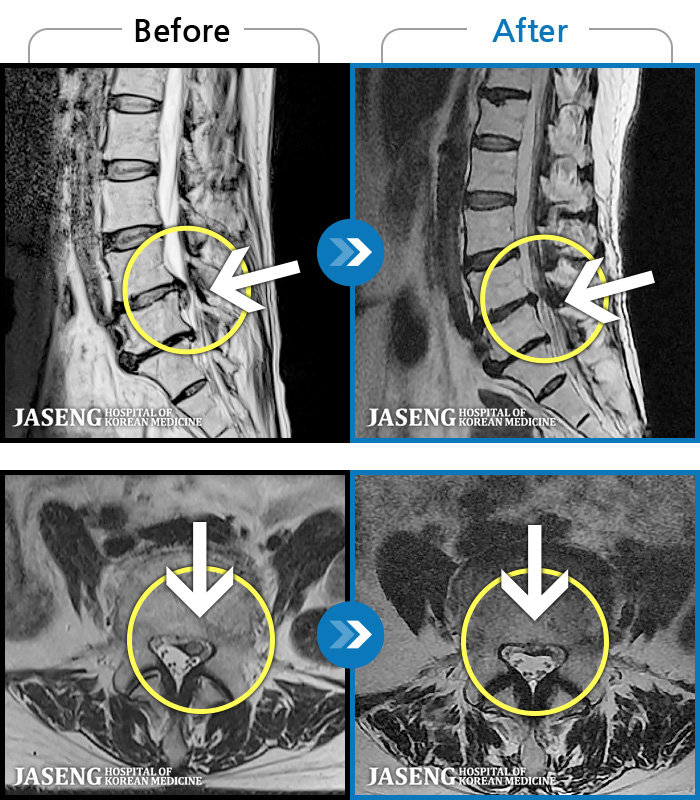

[] 03.04.01~09.11.01